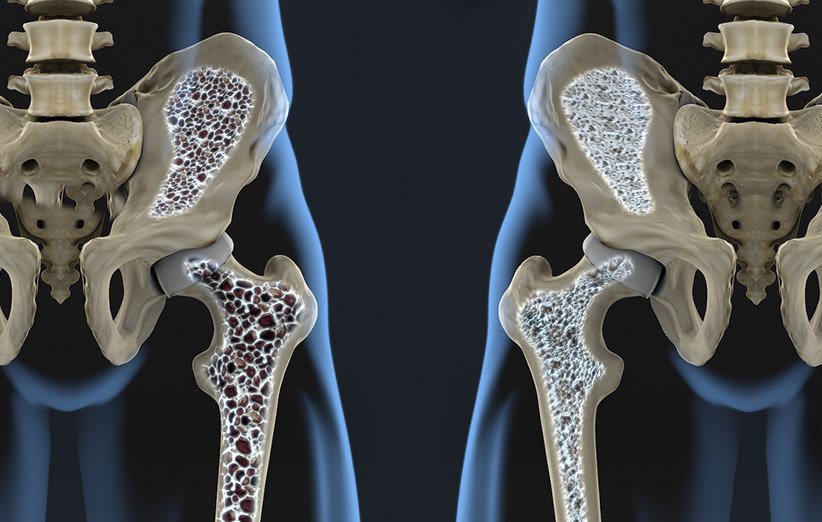

وی ادامه داد: وقتی فرد پوکی استخوان دارد ، حجم استخوان فرد کاهش می یابد و سر خوردن و شکننده است ، این بیماری به طور معمول در زنان و بعد از یائسگی تشدید می شود اما همچنین ممکن است در سنین پایین دیده شود. شیوع کمتری در مردان وجود دارد و برخی از مشکلات اساسی را دنبال می کنند.

پوکی استخوان

متخصص جراحی زانو اذعان کرد: شناسایی پوکی استخوان و پیشگیری از پوکی استخوان هشدار می دهد که میانی و سالمندان. در صورت عدم تشخیص و درمان ، این بیماری ممکن است منجر به شکستگی ستون فقرات ، ران و استخوان های دیگر با یک تروما ساده یا سقوط شود.

وی گفت: در مواردی که بیمار دیر می آید و پوکی استخوان در مراحل پیشرفته تری قرار دارد ، علاوه بر این درمان ها ، از داروهای خاص ممکن است برای جلوگیری از پیشرفت بیماری و بازگرداندن تراکم استخوان به شرایط عادی استفاده شود. شدت پوکی استخوان معمولاً با کمک آزمایش چگالی استخوان و علائم بالینی انجام می شود و نقش مهمی در تعیین فرایند مناسب برای هر بیمار ایفا می کند.